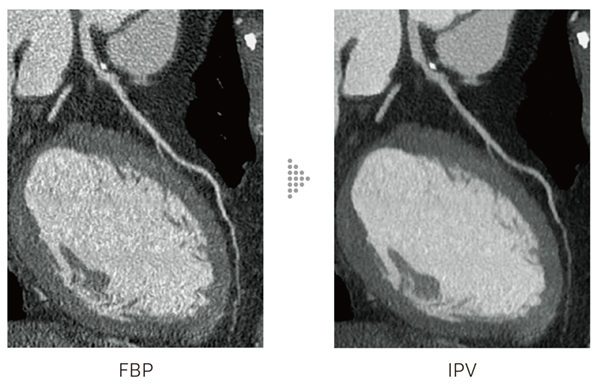

IPV*5はAI技術を活用して開発した画像再構成技術です。充分な反復処理により得られる画像を教師データとして,高精度の処理を高速化しました。

AI技術を活用した*4心臓CTの被ばくの低減

富士フイルムのAI技術を活用したIPV*4*5を心臓CTに適応することで,低管電圧撮影や低線量下での撮影においても,低ノイズで質感が維持された高画質を実現。

*5 IPVはIterative Progressive reconstruction with Visual modelingの略称です。

IPV:AI技術を活用して設計された逐次近似処理